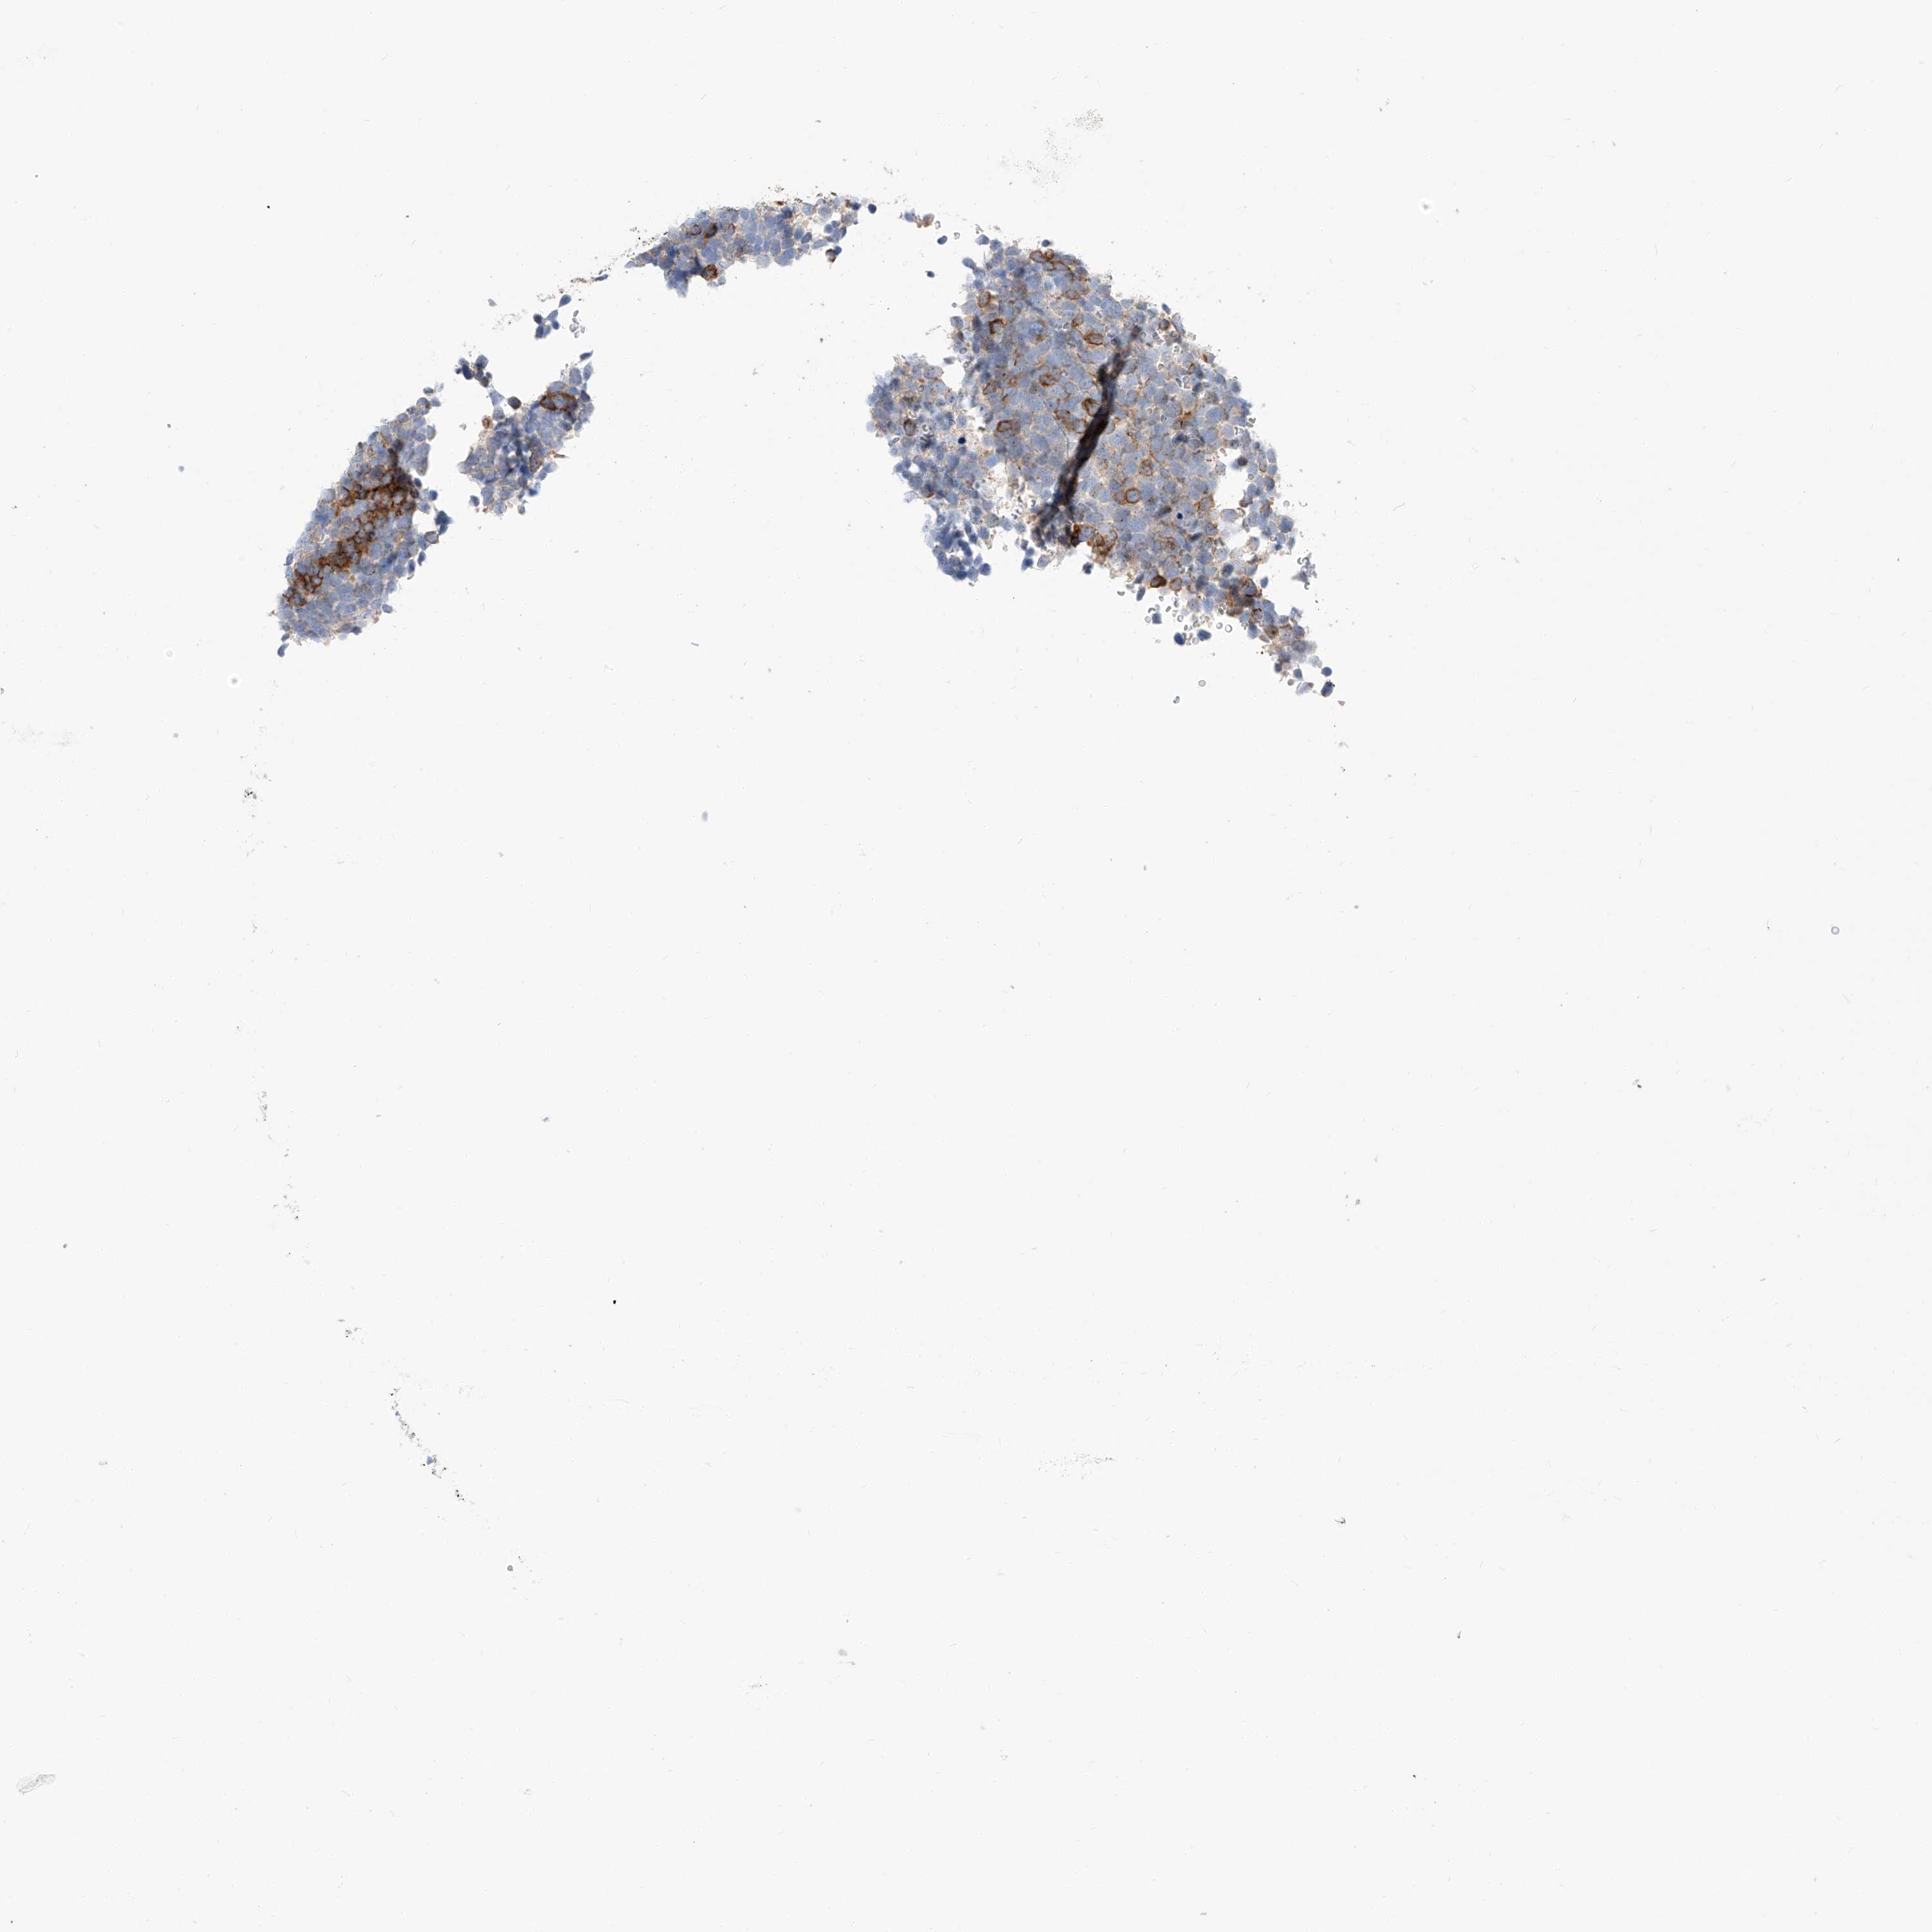

UROTHELIAL CANCER - Protein expressioni

A mouse-over function shows sample information and annotation data. Click on an image to view it in a full screen mode. Samples can be filtered based on level of antibody staining by selecting one or several of the following categories: high, medium, low and not detected. The assay and annotation is described here.

Note that samples used for immunohistochemistry by the Human Protein Atlas do not correspond to samples in the TCGA dataset.

Antibody stainingi

Antibody staining in the annotated cell types in the current human tissue is reported as not detected, low, medium, or high, based on conventional immunohistochemistry profiling in selected tissues. This score is based on the combination of the staining intensity and fraction of stained cells.

Each image is clickable and will lead to virtual microscopy that enables deeper exploration of all samples and also displays staining intensity scores, fraction scores and subcellular localization as well as patient and tissue information for each sample.

Antibody HPA029712

Antibody HPA029713

Staining

High

Medium

Low

Not detected

Intensity

Strong

Moderate

Weak

Negative

Quantity

>75%

75%-25%

<25%

None

Location

Nuclear

Cytoplasmic/membranous

Cytoplasmic/membranous,nuclear

Urothelial carcinoma, High grade